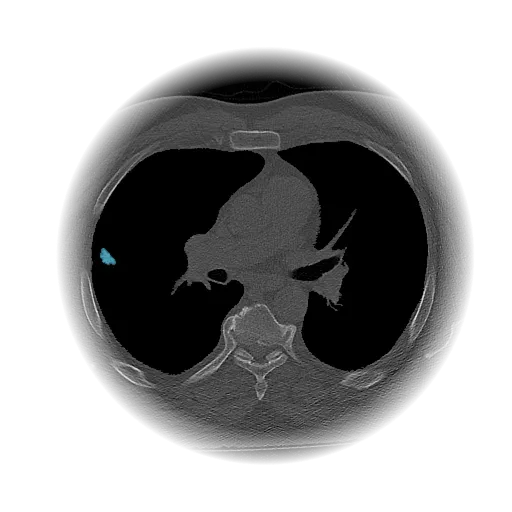

Lung Nodule Detection and Tracing Across Scans

Obvios.ai utilizes cutting-edge artificial intelligence to meticulously detect and track lung nodules, facilitating swift and precise diagnostics, thereby ensuring superior care and timely intervention for patients.